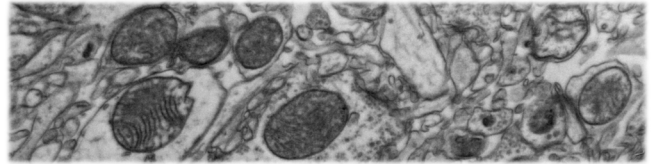

- New research reports activation of Ca2+ phosphatase Calcineurin regulates Parkinson’s-associated Parkin translocation to mitochondria & mitophagy (in flies); Genetic activation of Calcineurin boosts basal mitophagy (Click here to read more about this).

- New paper reports partial loss of the mitochondrial calcium uniporter (MCU) mitigates pathology in vivo across a diverse range of Drosophila models of neurodegenerative disease (including Parkinson’s); “MCU & NCLX are druggable entities” (Click here to read more about this).